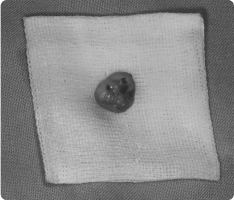

입안에도 혹처럼 불필요한 덩어리(종양)가 생길 수 있습니다.

그 중 흔히 볼 수 있는 것이 섬유종과 유두종입니다.

- 섬유종 : 잇몸, 뺨 안쪽, 혀 등에 자주 생기며, 오래된 자극(씹힘, 틀니, 교정 장치 등) 때문에 발생하는 경우가 많습니다.

- 유두종, 사마귀종 : 바이러스 감염이나 잦은 자극으로 인해 작은 사마귀처럼 돌출되는 양상을 보입니다.

대부분 양성(암 아님) 이지만, 크기가 커지거나 불편하면 제거하는 것이 좋습니다.

- 국소마취 후 병소 부위를 작게 절개하여 종양만 제거합니다.

- 필요한 경우 조직검사를 통해 정확한 진단을 확인합니다.

- 수술은 짧고 안전하게 진행되며, 회복도 빠릅니다.